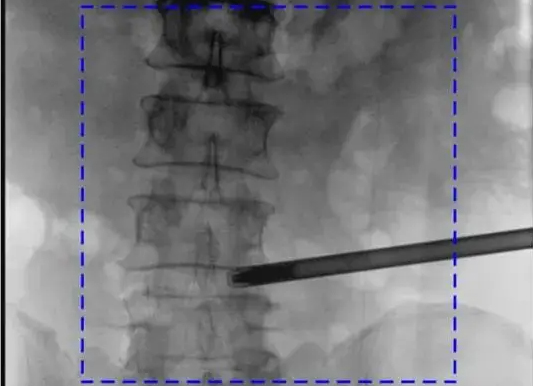

C臂机图像不清楚的常见原因及解决办法

C臂机作为骨科手术和介入治疗的核心影像设备,其图像质量直接影响临床诊断的准确性。医院在使用C臂机时,如果遇到图像不清楚的情况,多半是有以下这些原因导致的(附解决办法)。...